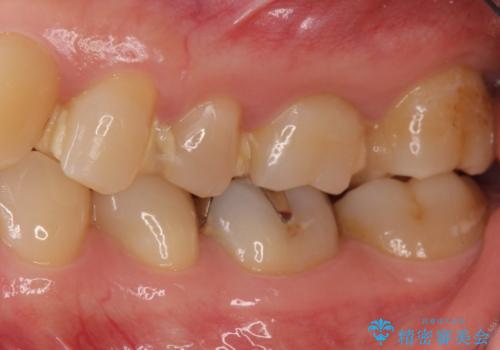

目立たない白いものがご希望とのことで、セラミックインレーで修復しました。

- 21万円(左上567:セラミックインレー 7万円x3本)費用は治療当時の料金となります

仮づめの状態でしたが、そこまで中は虫歯になっておらず、神経の治療も不要でした。

- かみ合わせや歯ぎしりが強すぎる方はセラミックが割れてしまう可能性があります